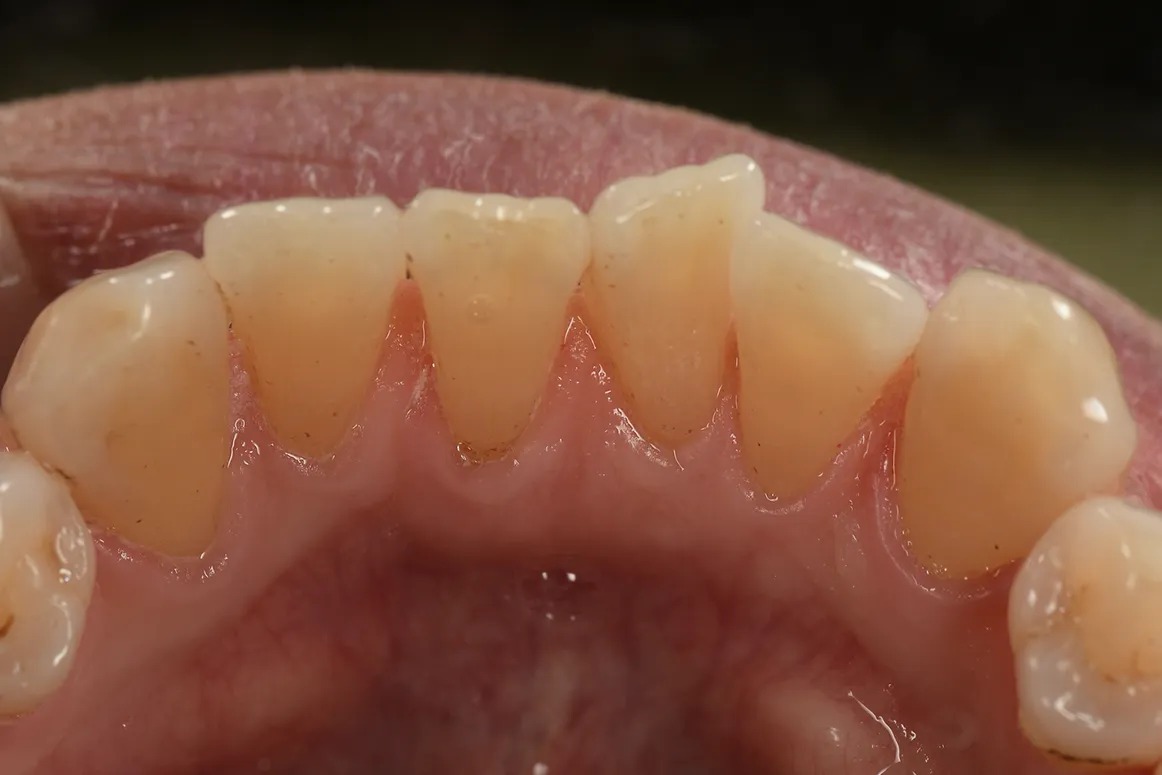

着色汚れが気になり、エアフローで

除去した症例①

主訴

着色汚れが気になる

治療内容

エアフロー